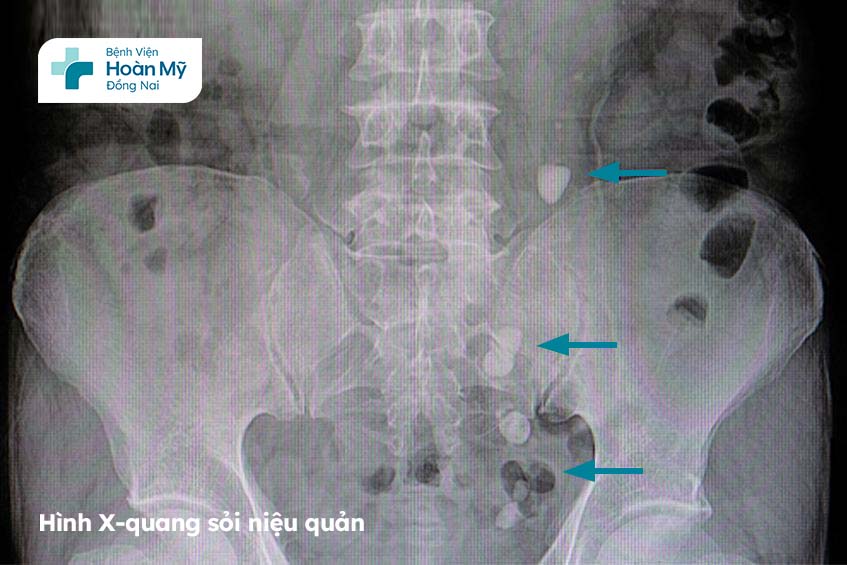

Hình ảnh X-quang của sỏi niệu quản Bệnh viện Hoàn Mỹ Đồng Nai